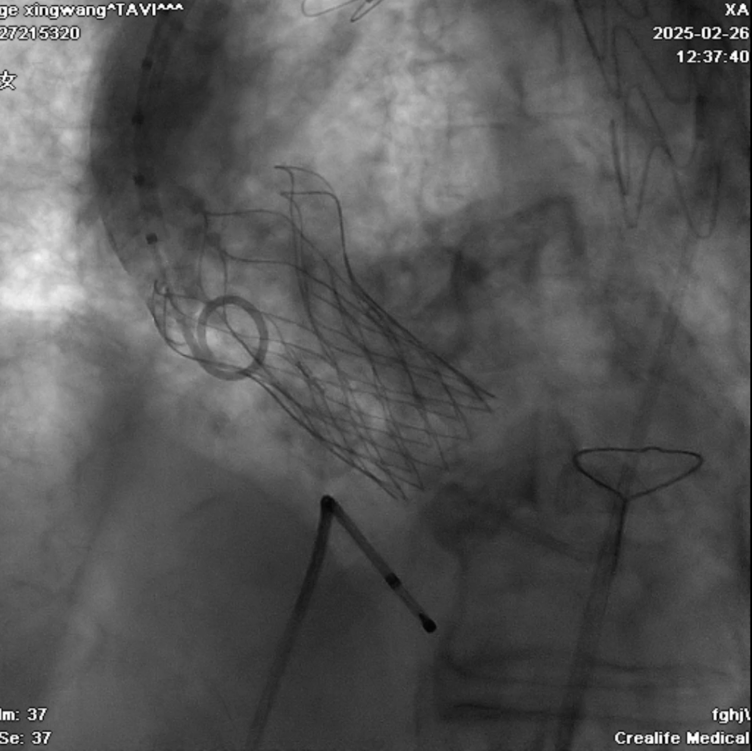

患者为77岁男性,因“反复出现活动后胸闷气喘3月”入院。患者入院后相关检查提示病情较为复杂:先天性主动脉瓣二瓣化伴重度主动脉瓣狭窄+主动脉穿透性溃疡+重度肺部疾病,考虑到外科手术风险极高,经心血管内科3病区梁有峰主任团队和相关科室充分讨论,决定采用一站式TAVR+TEVAR手术方案。手术由心血管内科联合心脏外科、麻醉科、心脏超声科,重症医学科等多学科团队共同完成。手术团队首先在主动脉溃疡破口处精准释放覆膜支架,随后经股动脉入路,成功完成经导管主动脉瓣置换术,应用介入微创技术一次性解决了主动脉瓣重度狭窄及主动脉穿透性溃疡等问题,整个手术过程顺利,术后第二天由ICU病房转入普通病房,目前患者已康复出院。